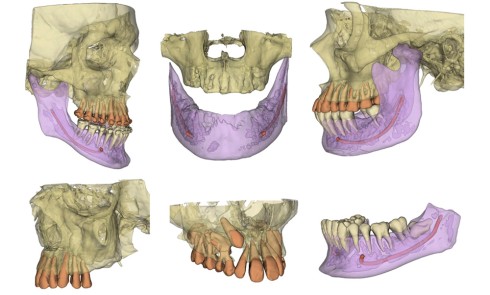

Article réservé à nos abonnés Prise en charge occluso-prothétique des conséquences orales et maxillo-faciales du bruxisme : apport de la prothèse amovible de recouvrement

Le bruxisme est défini comme le grincement parafonctionnel des dents, ou encore comme une habitude orale composée de tapotements, de...